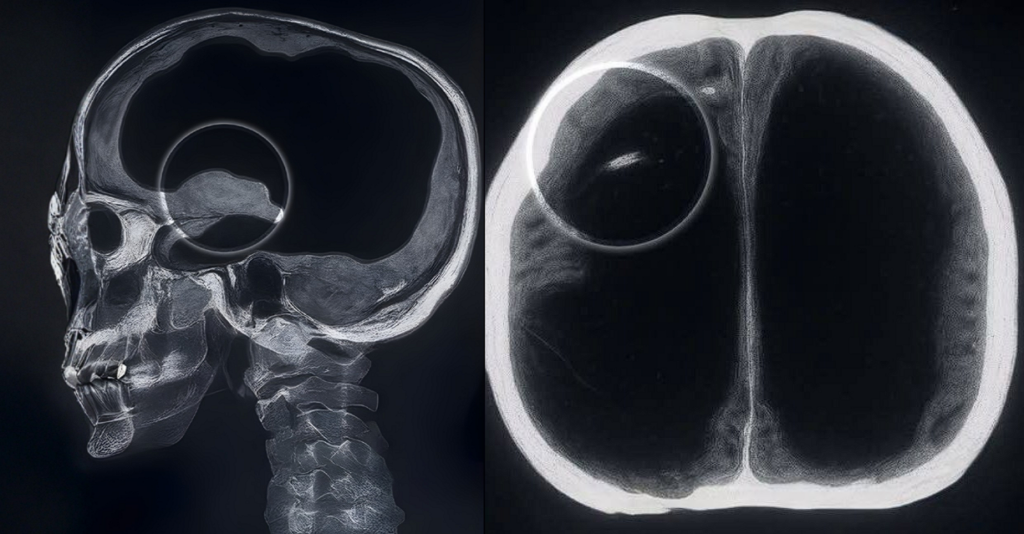

A investigação começou quando os médicos solicitaram uma tomografia e, em seguida, uma ressonância magnética. As imagens mostraram que grande parte da cavidade craniana estava tomada por líquido cefalorraquidiano. O tecido cerebral restante aparecia comprimido nas bordas do crânio. A equipe inicialmente ficou desconcertada, já que o padrão lembrava quadros graves de hidrocefalia, porém o paciente não apresentava os sintomas severos geralmente associados ao problema.

A condição foi identificada como um caso extremo de hidrocefalia crônica evolutiva. Durante a infância, o homem possuía um shunt para drenar o excesso de líquido, mas o dispositivo foi removido anos depois, o que permitiu que o acúmulo retornasse de forma lenta e contínua. Como o aumento ocorreu ao longo de décadas, o cérebro teve tempo para se adaptar, ocupando o espaço disponível e preservando parte das funções essenciais.